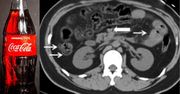

22-latek wypił drinka. Ten miał mu pomóc ochłodzić się w upalny dzień. Nie spodziewał się jednak, że zakończy się to dla niego tragedią. Jednak to nie Coca-Cola miała bezpośredni związek ze śmiercią 22-latka, jak twierdzą chińscy badacze, lecz ukryta choroba, która przypadkiem ujawniła się po wypiciu napoju, uważają brytyjscy lekarze.